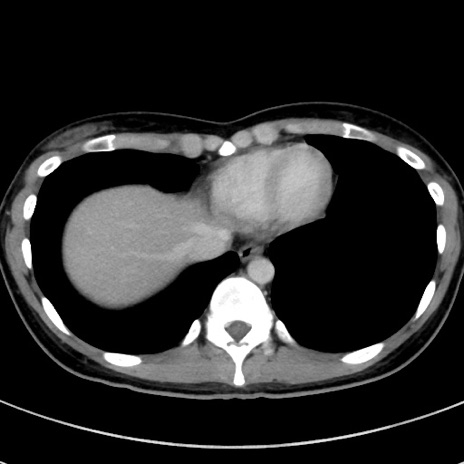

症例17(横断像)

【症例】20歳代女性

【主訴】嘔吐、下腹部痛

【現病歴】昨日夕食後に嘔吐し下腹部痛が出現。本日になっても嘔吐持続し改善しないため来院。

【身体所見】意識清明、BT 37.2℃、BP 108/67mmHg、腹部:平坦、やや硬、下腹部正中から右にかけて圧痛あり、反跳痛軽度あり、tapping pain(+)。

【データ】WBC 13600、CRP 14.94